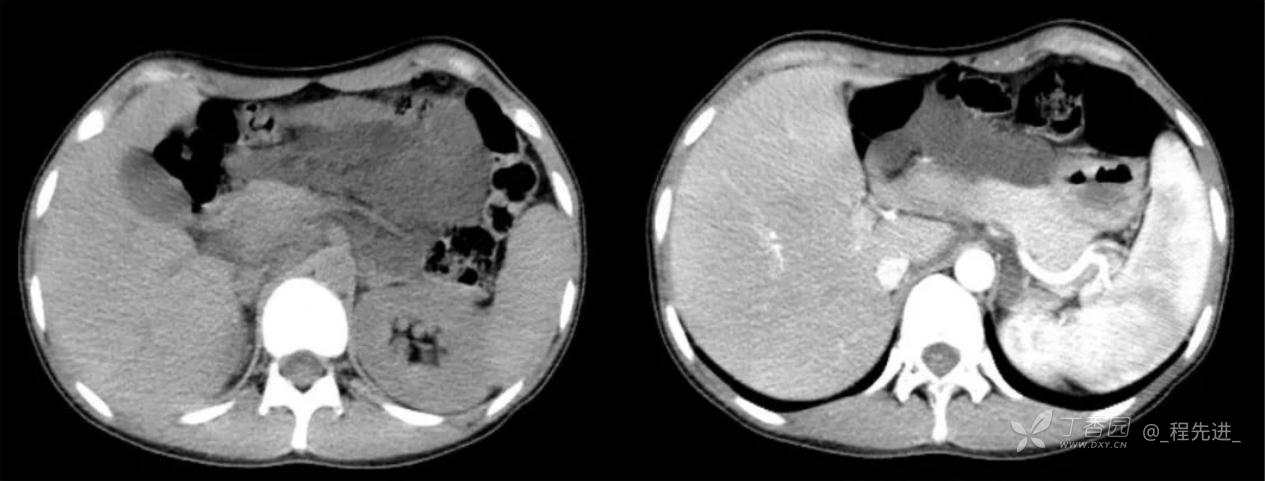

主诉:腹痛、发热一天

现病史:一天前无明显诱因出现腹痛并发热不适,伴恶心、干呕,诊所肌注药物(具体用药不详),无缓解,无明显尿频、尿痛。

体格检查:腹肌稍紧张,右上腹部轻压痛,右肾区叩痛